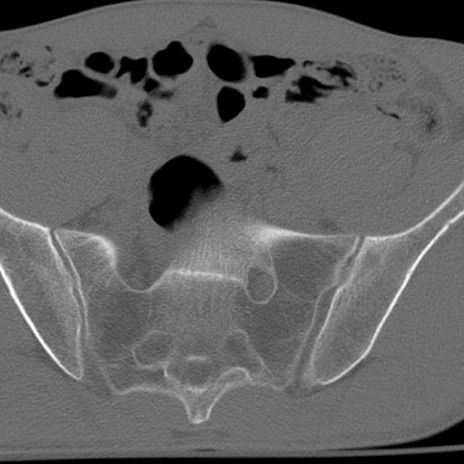

症例3 腰椎CT(横断像)

腰椎CT